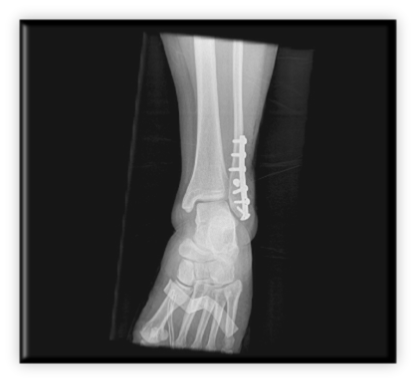

Κάταγμα κάτω πέρατος περόνης (έξω σφυρού) παρεκτοπισθέν με ταυτόχρονη παρεκτόπιση προς τα έξω του αστραγάλου. Αντιμετωπίστηκε με ανοικτή ανάταξη και εσωτερική οστεοσύνθεση με πλάκα – βίδες και μία διακαταγματική βίδα συμπίεσης

ΚΑΤΑΓΜΑ ΕΞΩ ΣΦΥΡΟΥ ΑΝΤΙΜΕΤΩΠΙΣΘΕΝ ΣΕ ΧΕΙΡΟΥΡΓΕΙΟ ΜΑΧΗΣ ΣΤΟ ΑΦΓΑΝΙΣΤΑΝ ΑΠΟ ΤΗΝ ΕΛΛΗΝΙΚΗ ΑΠΟΣΤΟΛΗ 10. Ποδοκνημική - Άκρος πόδας Αρχική σελίδα 10. Ποδοκνημική - Άκρος πόδας Ορθοπαιδικές Παθήσεις 2. Ώμος 1. Αυχένας 3. Αγκώνας 5. Σπονδυλική στήλη 6. Ισχίο 7. Μηρός 8. Γόνατο 9. Κνήμη 10. Ποδοκνημική - Άκρος πόδας 4. Άκρα χείρα - Πηχεοκαρπική